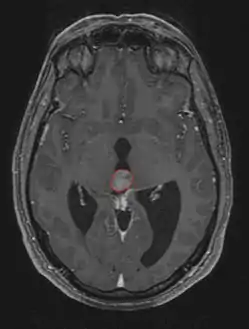

ورم الغدة الصنوبرية

ورم الغدة الصنوبرية Pinealoma هو ورم حميد عادة في الغدة الصنوبرية. تنتج الغدة الصنوبرية هرمون الميلاتونين الذي يلعب دوراً في تنظيم إيقاع الحياة اليومي. وقد يُعطّلُ ورمُ الغدة الصنوبرية إنتاجَ هذا الهرمون، و يسبب الأرق.[2]

التشخيص

من بين الأنواع المختلفة لأورام الغدة الصنوبرية، يبرز النوع الأكثر تفضيلاً عند التشخيص و هو ورم الخلية الصنوبرية.[7]